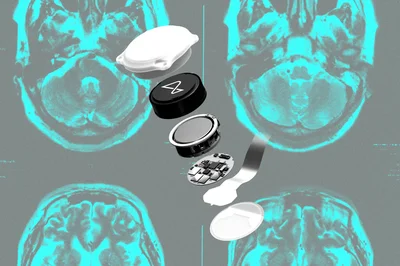

Breakthrough in Down Syndrome Treatment

Scientists at Beth Israel Deaconess Medical Center and Harvard Medical School have pioneered a novel CRISPR/Cas9 method to silence the extra 21st chromosome causing Down syndrome. This groundbreaking proof of concept could pave the way for the first effective treatment of this common genetic disorder. While still in early stages, the research marks a major step forward in genetic medicine. Experts are optimistic about future clinical applications that could transform lives.